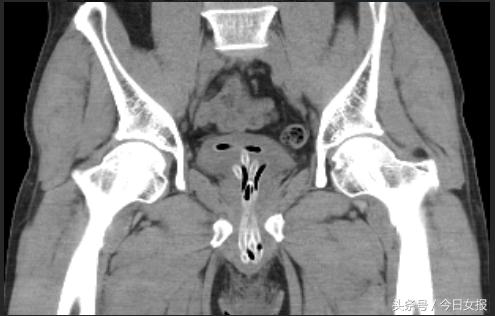

刘先生不好意思跟家人说起,也不好意思到医院求助,直到一天后排尿不出、疼痛剧烈、尿道流血、阴囊肿胀才来到位于湖南省人民医院马王堆院区的泌尿外四科求助。经过检查发现,刘先生身体里余留下的橡胶管,像多条蚯蚓一样扭曲着阻塞在尿道和膀胱里,泌尿外四科负责人杨科主任当即表示,事情非常紧急,异物必须马上取出。随后,立马在刘先生入院当天便进行了急诊手术治疗。

因管子又粗又长,且在尿道内迂曲达7折,以杨科为首的医疗团队经过详细讨论,决定为刘先生实施膀胱切开+尿道膀胱镜手术。经过1个多小时的手术,顺利取出了半米多长的橡皮管,手术之后刘先生紧缩的眉头终于舒展开了。